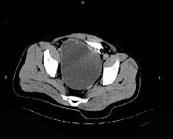

问题 男,34岁,右下腹持续性隐痛半月,排尿时加重入院,CT检查如图所示,下列说法错误的是 ( )

选项 A、该囊性病变考虑来源于精囊 B、此囊性病变为右精囊腺囊肿 C、膀胱右后下方囊性病变 D、膀胱向下,向后移位 E、右肾缺如

答案 D